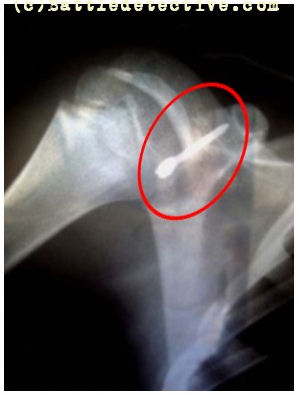

Flechettes are small nail sized

They weigh 0.0017oz and measure just

over an inch. The X-Ray shows impact

on a person. |